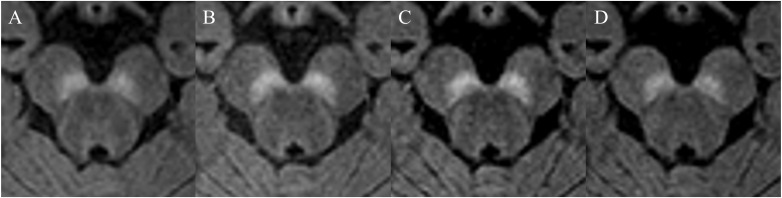

Methods: Neuromelanin images with MT pulse and SPIR (flip angles [FAs] = 19º, 22º, and 25º) were acquired from 30 healthy volunteers. To achieve the same acquisition time of 5 min, the slab thickness of the MT images was less than 1/3 of those of the SPIR images; the acquisition areas for MT and SPIR were the brainstem and the whole brain, respectively. Visual and quantitative evaluation was performed and compared on the four sequences acquired for the substantia nigra pars compacta (SNc) and the locus coeruleus (LC). For visual assessment, we used the mean score from a 3-point scale by two evaluators. For quantitative evaluation, the contrast ratios of SNc and LC were calculated in comparison with the background tissue signal.

Results: In visual assessments, the mean scores of the SPIR FA19º and FA22º images were better than others in the SNc. Regarding LC, the SPIR FA22º image yielded the best mean score. In quantitative evaluations, the MT image was significantly lower than the other three images in SNc. Regarding LC, there were no significant differences among the four acquired images (MT and SPIR FA19º, FA22º, and FA25º).

Conclusions: Detection of neuromelanin in SNc and LC was improved by the use of SPIR compared to MT pulse in 3D neuromelanin imaging.